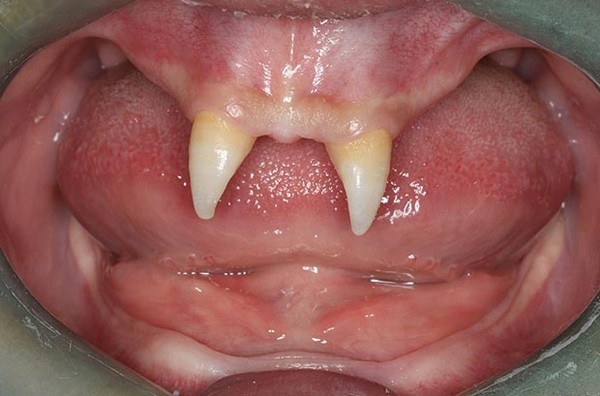

Một cậu bé 16 tuổi tên Wang Pengfei sống tại Trùng Khánh, Tây Nam Trung Quốc đã mắc một chứng bệnh lạ từ khi sinh ra. Căn bệnh này khiến Pengfei có rất ít tóc và đến thời kỳ mọc răng, cậu chỉ mọc duy nhất 2 chiếc răng cửa sắc nhọn như… ma cà rồng.

Hàm răng kỳ lạ của Wang Pengfei chỉ có duy nhất 2 chiếc răng cửa nhọn hoắt.

Do căn bệnh này, cuộc sống của Wang Pengfei gặp rất nhiều khó khăn. Bên cạnh đó, tình cách củaPengfei cũng trở nên kỳ quặc, Bà Wang Hui cho biết: “Từ nhỏ, Pengfei đã không có bạn và khi lớn lên nó mới nhận ra mình khác biệt với người khác. Con trai tôi này càng cô lập với mọi người. Nó luôn thấy xấu hổ về hàm răng của mình và thậm chí sẵn sàng tấn công những ai trêu chọc hay bàn tán về nó”.

Trong khi đó, các bác sĩ ở bệnh viện Tây Nam cho biết, chỉ khi nào Pengfei đủ tuổi trưởng thành mới có thể tiến hành phẫu thuật. Dự kiến chi phí cho ca phẫu thuật này là khoảng 70.000 đến 80.000 nhân dân tệ (khoảng 234 đến 269 triệu VNĐ).